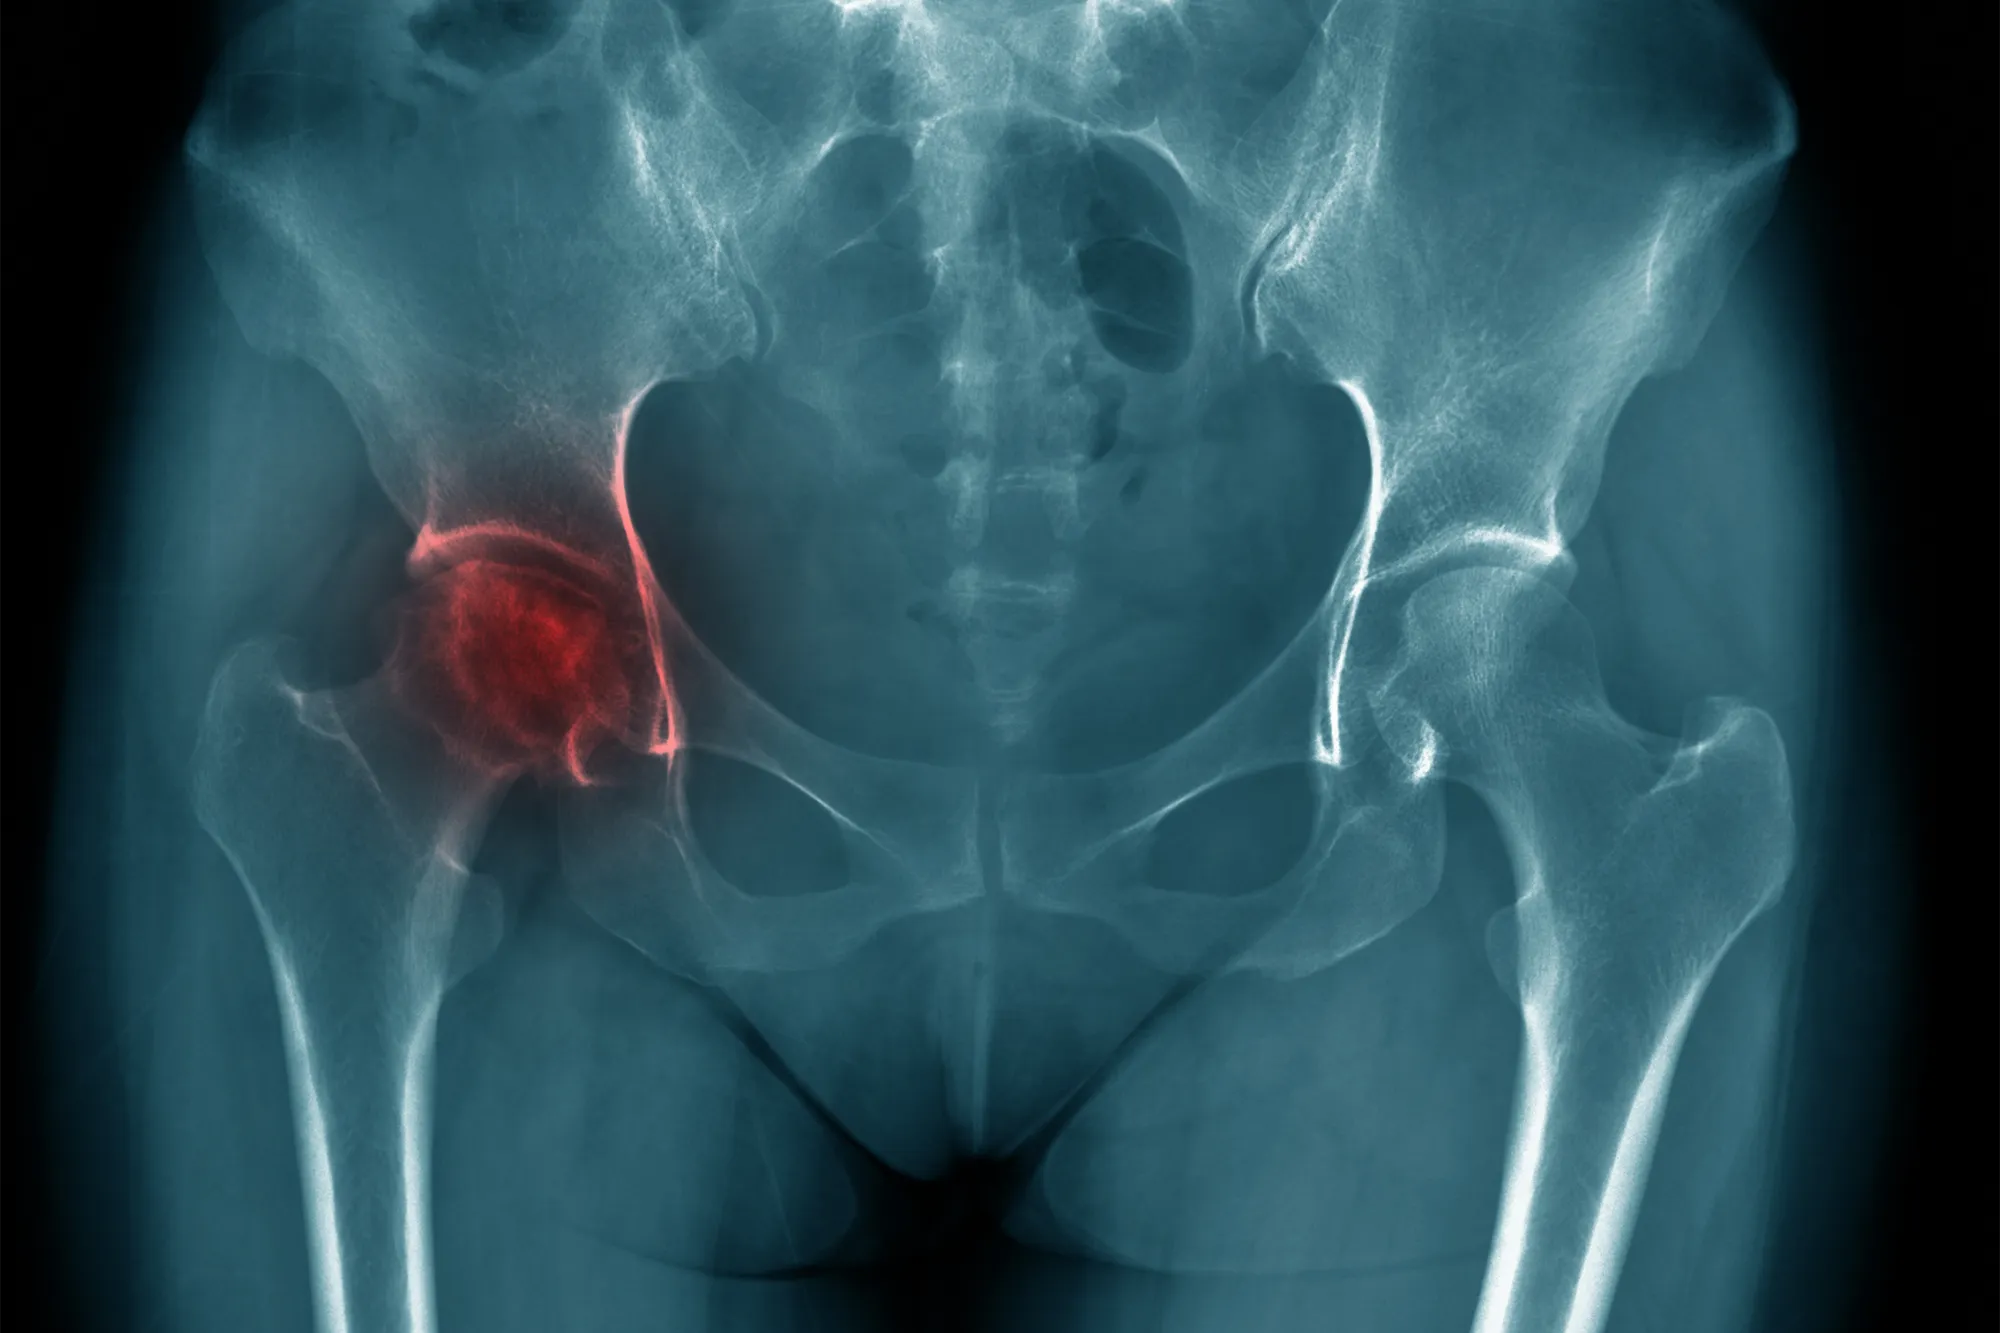

L’ONA évolue en plusieurs stades radiologiques correspondant à la classification de FICAT (ci-contre) :

- St 1: radiographies normales (ONA visible seulement à l’IRM)

- St 2: ONA visible à la radiolgraphie et sphéricité de la tête fémorale conservée.

- St 3: perte de sphéricité de la tête fémorale

- St 4: coxarthrose secondaire à l’ONA.